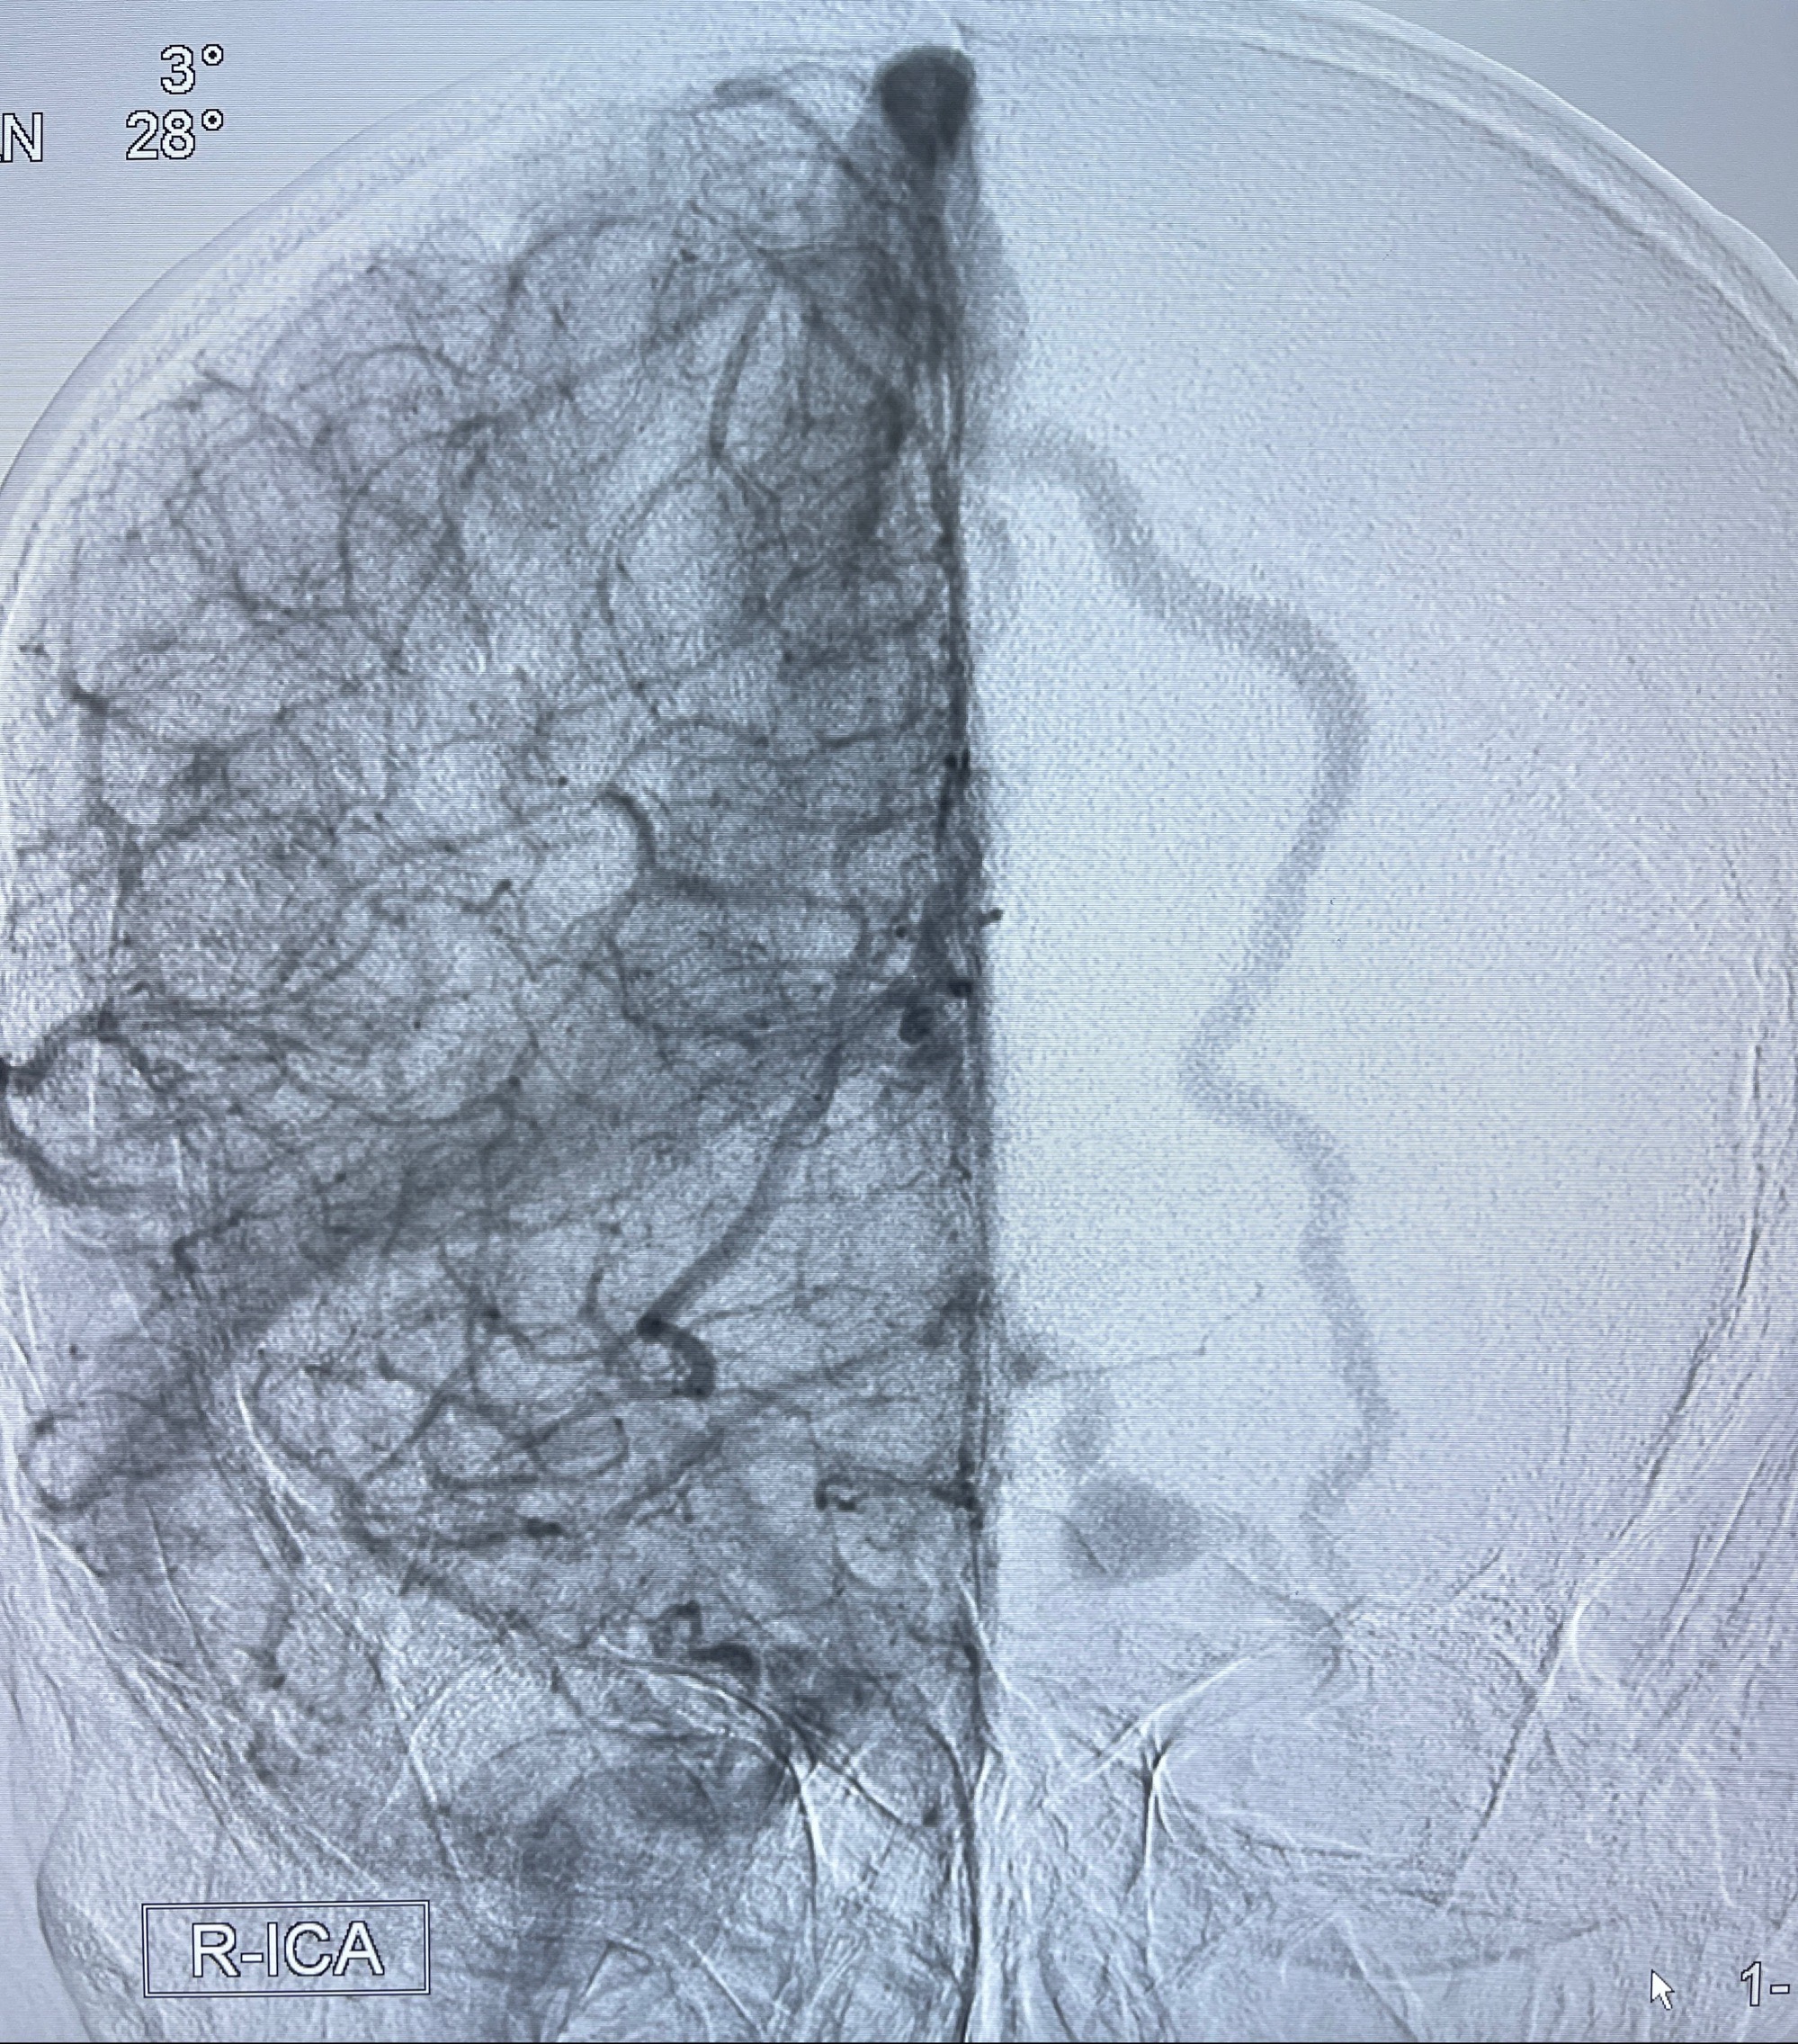

2023年8月21日]景德镇市第一人民医院脑血管造影检查,提示:主动脉弓、双侧颈总动脉、锁骨下动脉造影未见异常,左侧大脑前动脉静脉瘘。

2023-09-13全脑血管造影:前颅底硬脑膜动静脉瘘,供血动脉为双侧胼周动脉、眼动脉脑膜支,静脉向上矢状窦方向引流